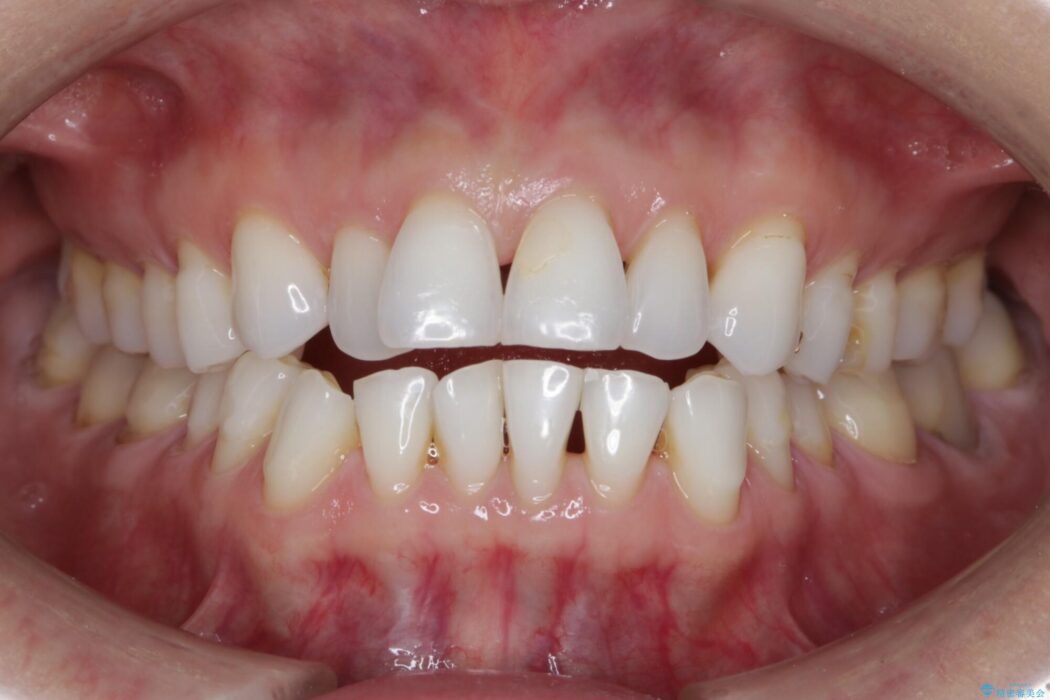

笑った時の歯の見た目がきれいになりとても喜んでいただけました。

診査したところ叢生だけでなく生まれつき永久歯の欠損、いわゆる先天欠如により歯の本数が少ないため噛み合わせなどにも影響が出ている状態でした。